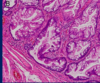

Q

מהו הממצא

A

פסאודו-סיצטה, ציסטה שאינה צלולה

**נראה בד”כ אחרי טראומה או דלקת לבלב

66

מה נראה במבט היסטולוגי בפוליפים מסול Sessile serrated

נראה כמו מגף בבסיס המוקוזה